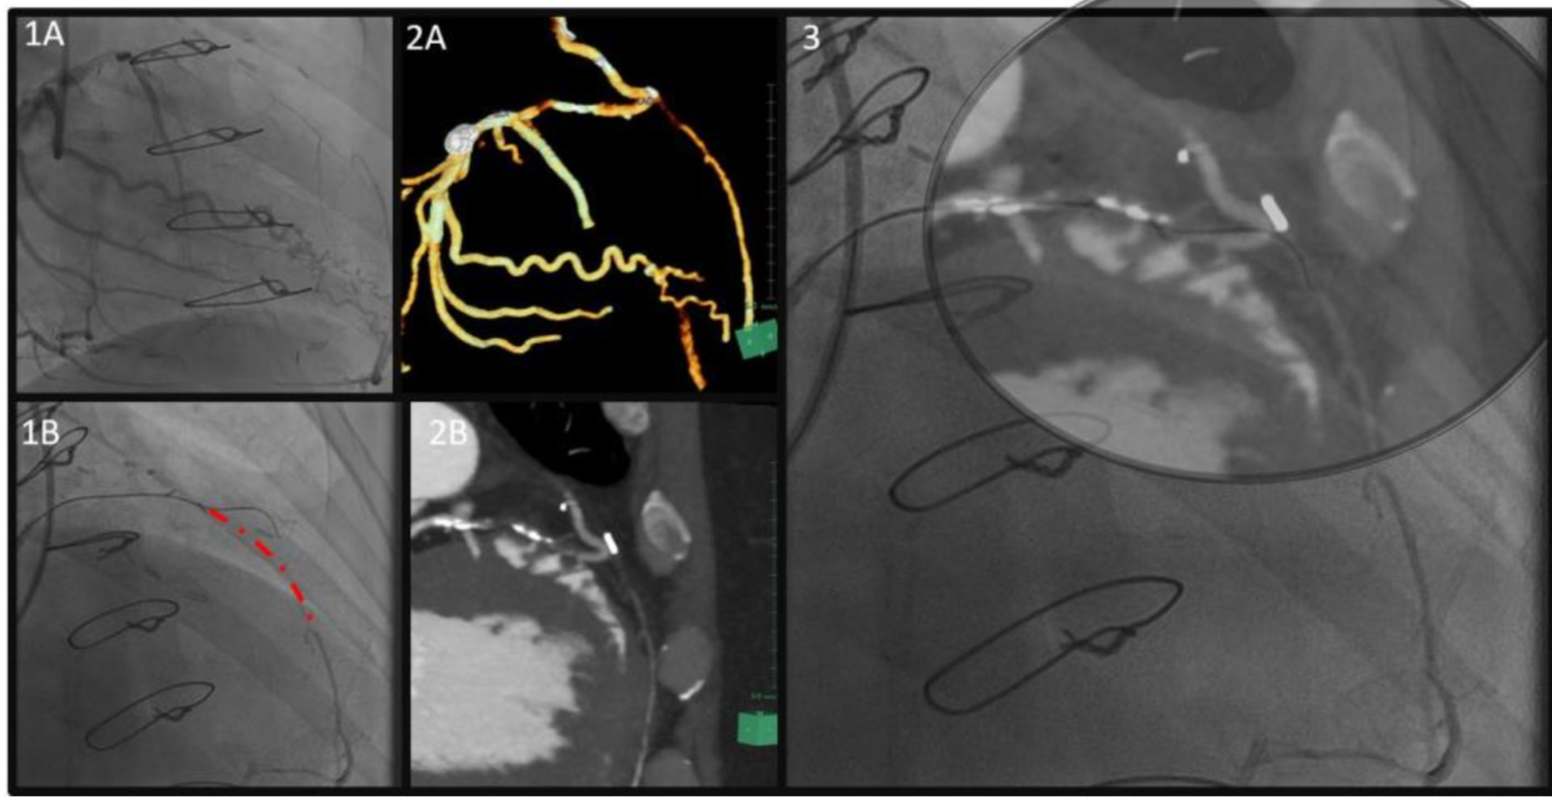

Angiographically, a proximal to distal long-occluded LAD with collateral filling from the left circumflex artery (LCX) (Figure 1A) was seen in addition to a severe LIMA-LAD anastomosis site stenosis. Preprocedural cardiac computed tomography (CT) showed significant tenting at the site of the LIMA anastomosis, along with heavy calcification in the mid part of the LAD (Figures 2A, 2B). Antegrade wire crossing of the mid calcified LAD (Gaia Third wire with Corsair-ProXS microcatheter [both Asahi Intecc]) was achieved. The wire was seen deflecting in a different pathway than the angiographically anticipated course of the vessel (Figure 1B). Therefore, the CT images were reanalyzed (Figure 2B). Surprisingly, the image combination showed that the wire was within the tented site of the LIMA-LAD anastomosis site and correctly positioned according to the vessel course (Figure 3). After further advancement of the wire, the recanalization was successfully completed (Figures 4A, 4B).